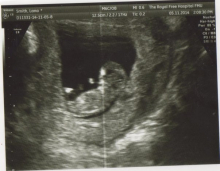

Baby Deaton

I have a healthy 10week and 4day old baby today I'm not quite 12 weeks so I wasn't able to have the full scan check the baby's heart spine brain wtc il being bought back in next week from 11weeks we should be able to see baby measuring 36cm and needs to be 46cm so we're back again next week sorry didn't post up Yesturday I heard his or her lil heartbeat 169beats per min amazing and so small moving and kicking about didn't like the intra sound head interfering in his or her sleep was amazing I'm in a world of my own atm thank you for all the love ladies Xxx